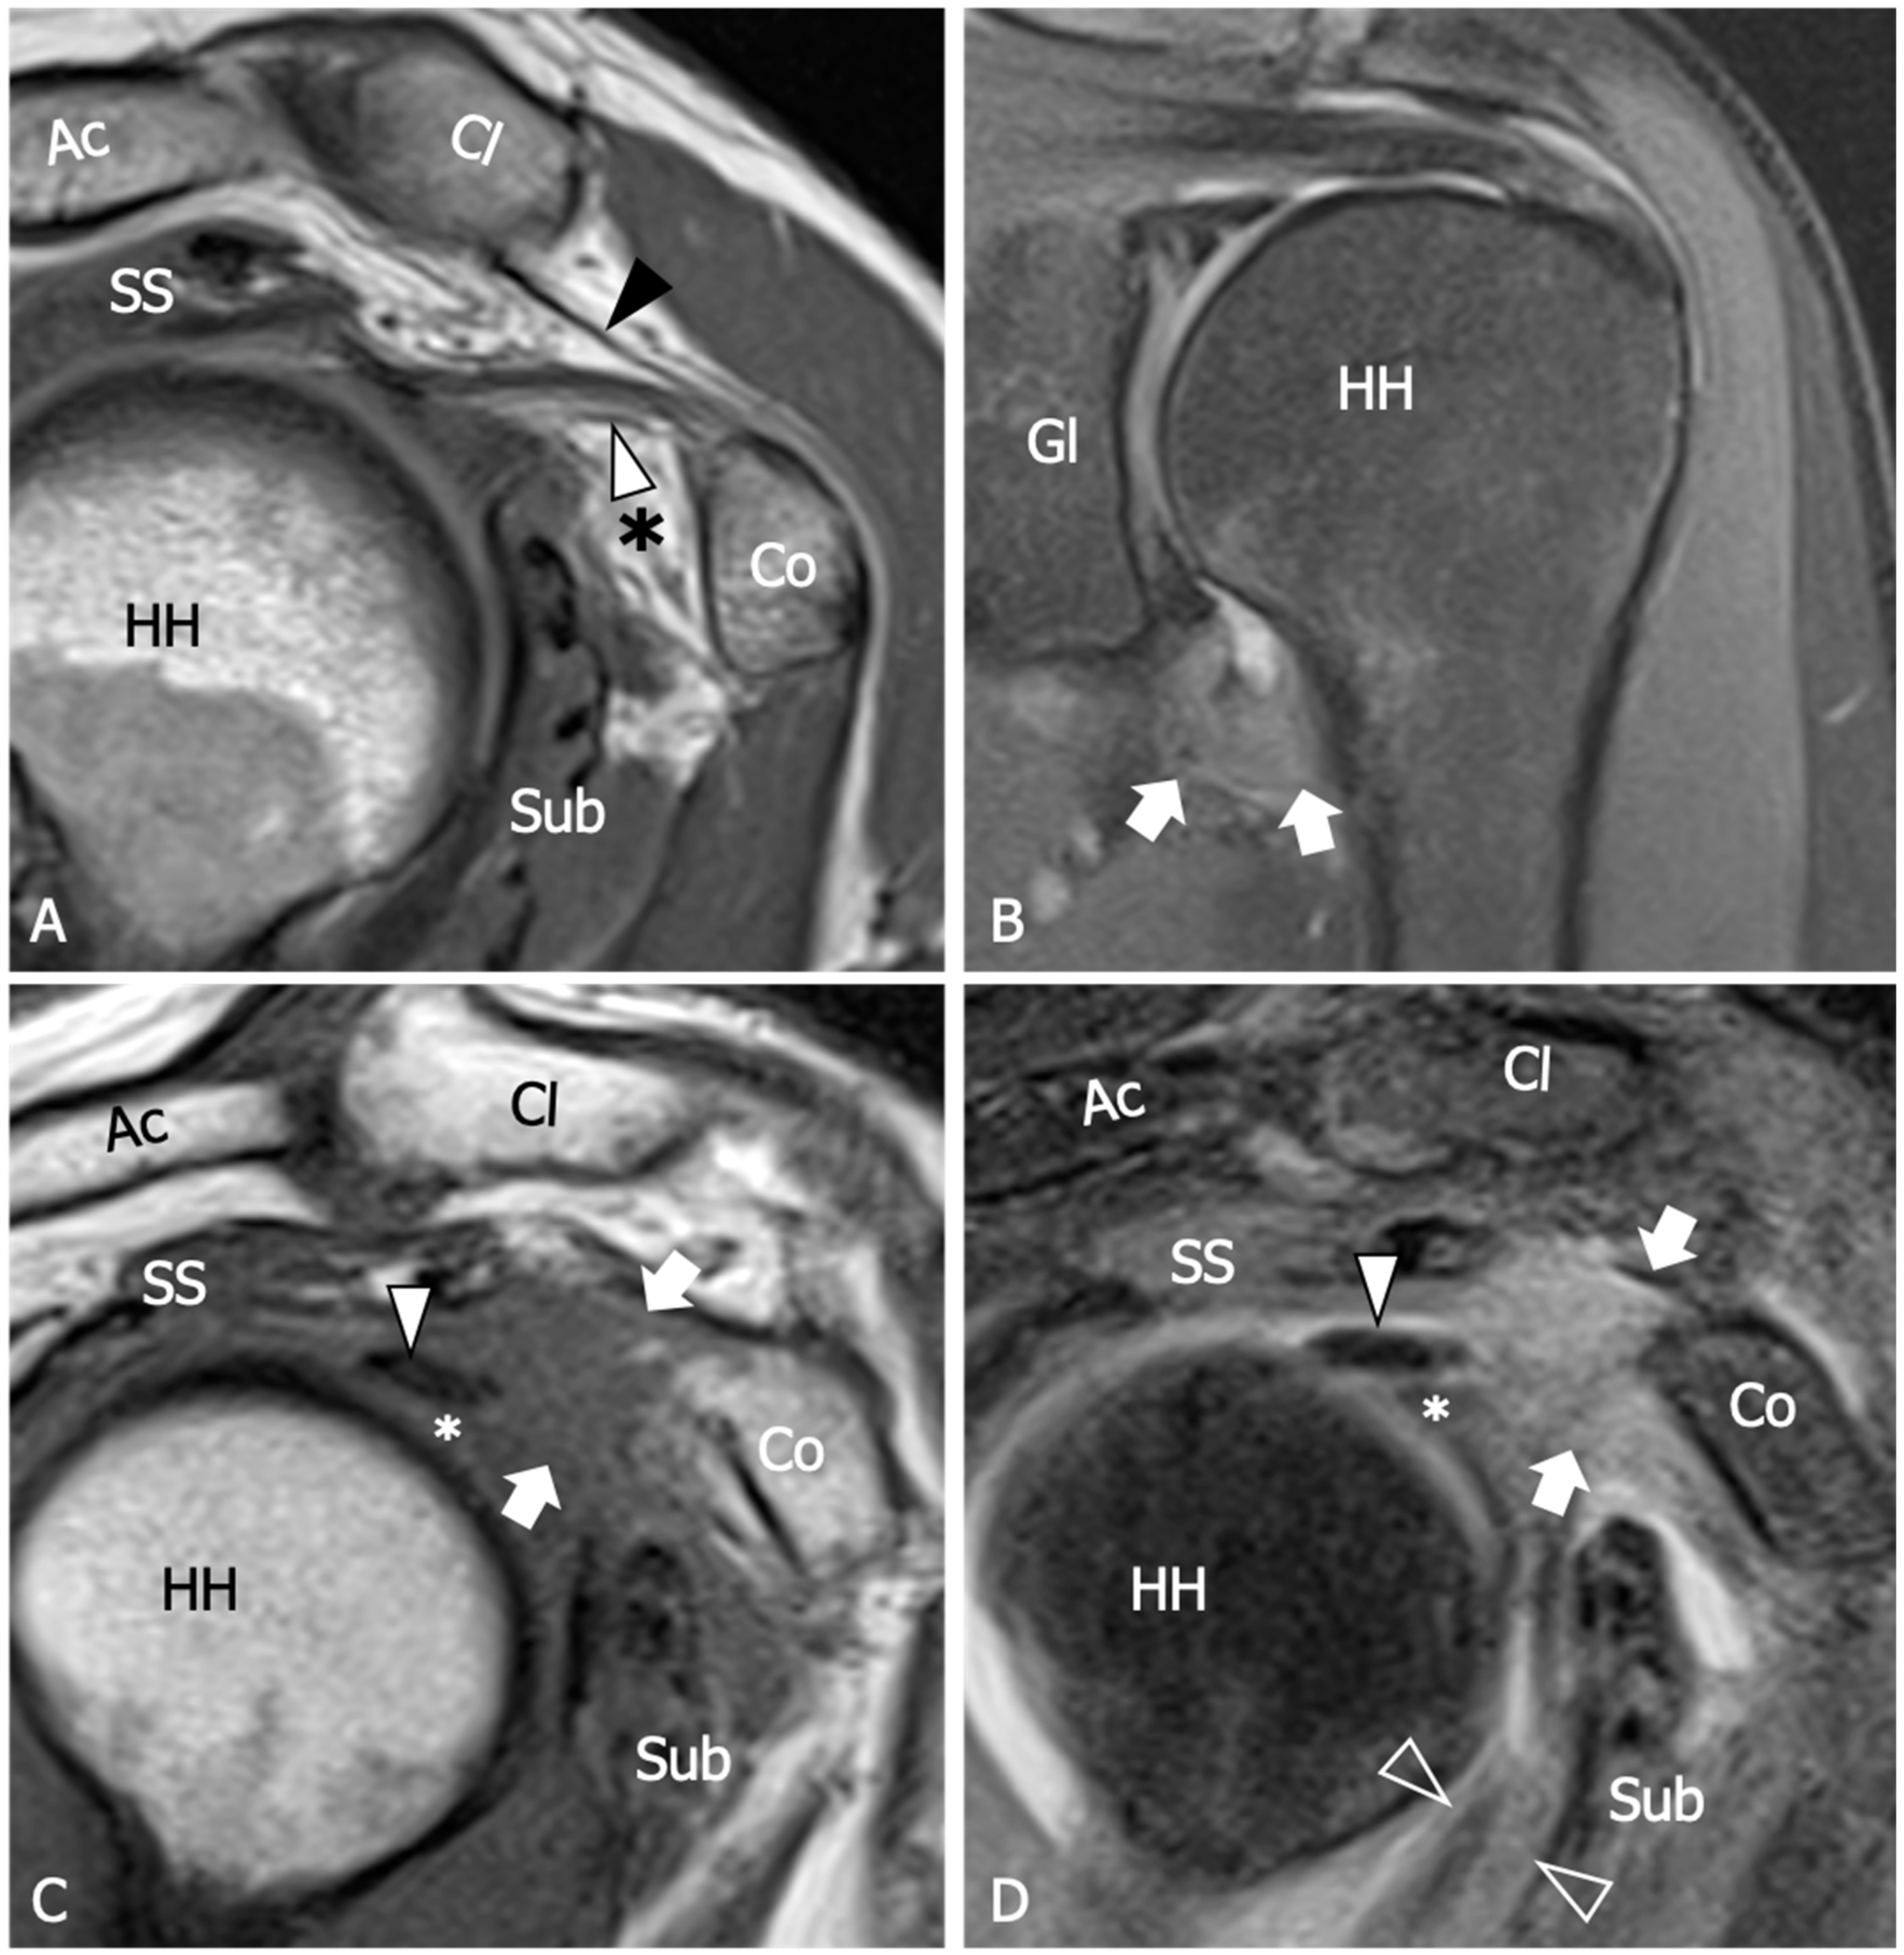

Figure 4.

Adhesive capsulitis in a 45 year old man with severe limitation of the glenohumeral ROM after a trauma, who was submitted for an MRA for a suspected labral tear. (A) Axial and (B) Coronal tSE fat-suppressed T1-weighted MR images obtained after intraarticular injection of gadolinium demonstrate anterior extravasation of the contrast medium (outlined arrows) into and underneath the subscapularis muscle (Sub) as a consequence of capsular stiffness and fissuration. Note the abnormally low distension of the axillary recess (arrows) and its markedly thickened walls. In (B) a partial thickness tear (white outlined arrowhead) of the articular side of the supraspinatus tendon (black arrowhead) is also evident. In effect, the tear involves both the inner fibers of the supraspinatus and the joint capsule, which are merged at this level to form the superior complex. As a consequence, note the superior migration of the contrast outside the joint cavity (black arrow). Black outlined arrowhead, long head of the bicep tendon; white arrowhead, subscapularis tendon; asterisk greater tuberosity; star, lesser tuberosity; HH, humeral head; Gl, glenoid; Ac, acromion.

Similarly, the utility of intravenous gadolinium in evaluating joint capsule vascularization and thickening is a topic of debate. Ahn et al. found a statistically significant positive linear correlation between the grade of axillary recess capsule enhancement, the thickness of the joint capsule, and pain intensity in individuals diagnosed with AC; however, no association was observed between the severity of limitation in forward elevation, external or internal rotation and the degree of axillary recess capsule enhancement [59]. Moreover, in another study, no substantial effects on the diagnosis of AC emerged between conventional MRI and gadolinium-enhanced MRI, despite the intravenous administration of contrast agent appearing to have some effect in increasing the reader’s confidence in measuring the joint capsule [60].

In conclusion, although MRA and MRI with intravenous contrast injection may provide additional information about the status of the capsule and may increase the reader’s confidence in diagnosing AC, conventional MRI without contrast administration has been proven to be accurate enough for diagnosis and should be preferred considering its lower invasiveness and cost [53,60].